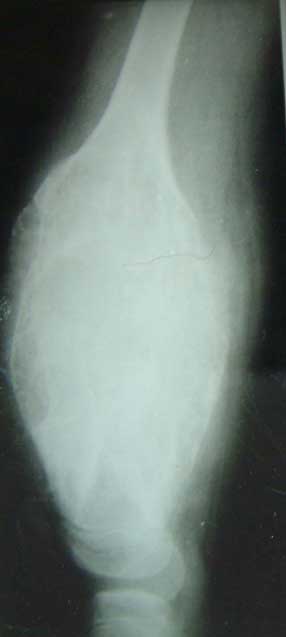

股骨远端骨母细胞瘤               段截肿瘤,大段异体骨移植术后3年,

骨愈合良好,并且获得良好的膝关节功能。